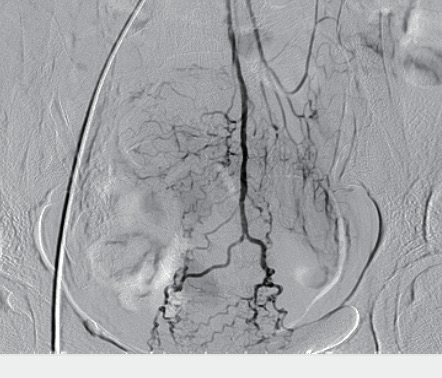

Эмболизация печёночной артерии:

Во время интервенционного лечения гепатоцеллюлярной карциномы

мобильная интервенционная C-дуга PLX C9100 обеспечила чёткую визуализацию сосудистой структуры и положения проводника. В результате время операции сократилось с 30 до 18 минут, а уровень облучения снизился примерно на 40%.